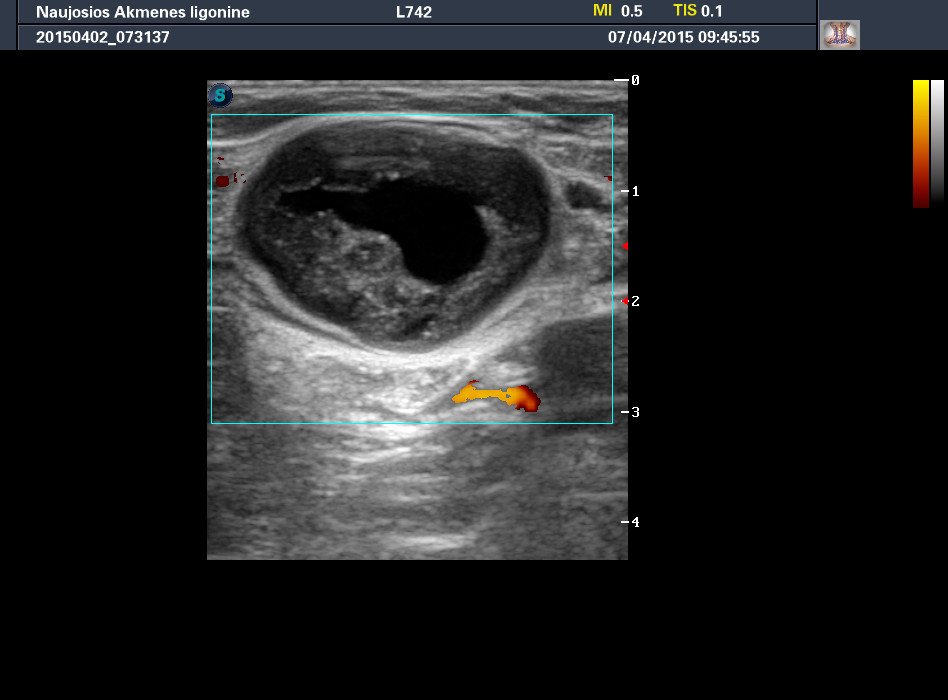

Мужчина средних лет. Жалуется на "гулю" в левой субингвинальной области и синяки на коже в бедра. Два дня назад были боли в левом бедре. Хирург направляет для исключения сосудистой мальформации.

При УЗИ в субингвинальной области слева определяется такое аваскулярное образование:

Далее, у пациента обнаружен двухсторонний крипторхизм, оба яичка в паховых каналах, без очаговой патологии.

Оперирован. Диагноз после операции - гнойное расплавление лимфатического узла.